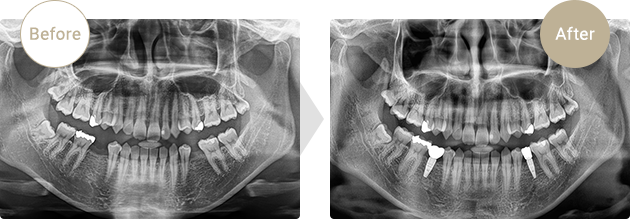

症例.01

下顎左右5番先天欠損部にインプラントを埋入しました。